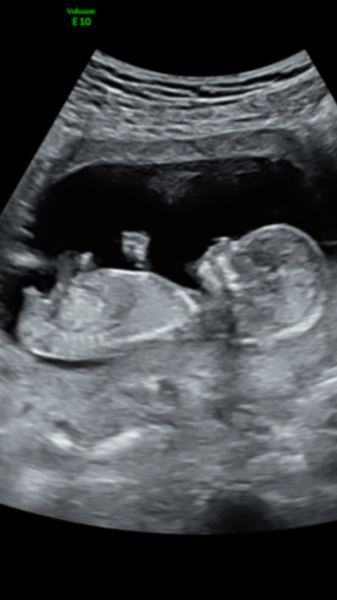

Vill ngn gissa den är i vecka 19(18+6 ) beräkna 18/2-18